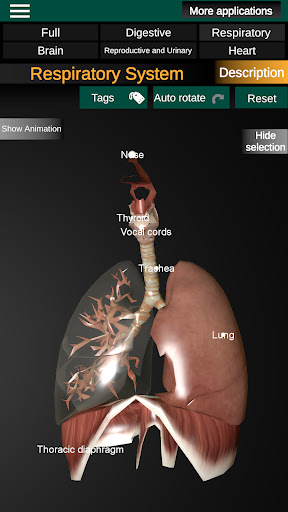

* Sistem pernafasan, yang meliputi trakea, bronkus, paru-paru dan animasi sistem ini.